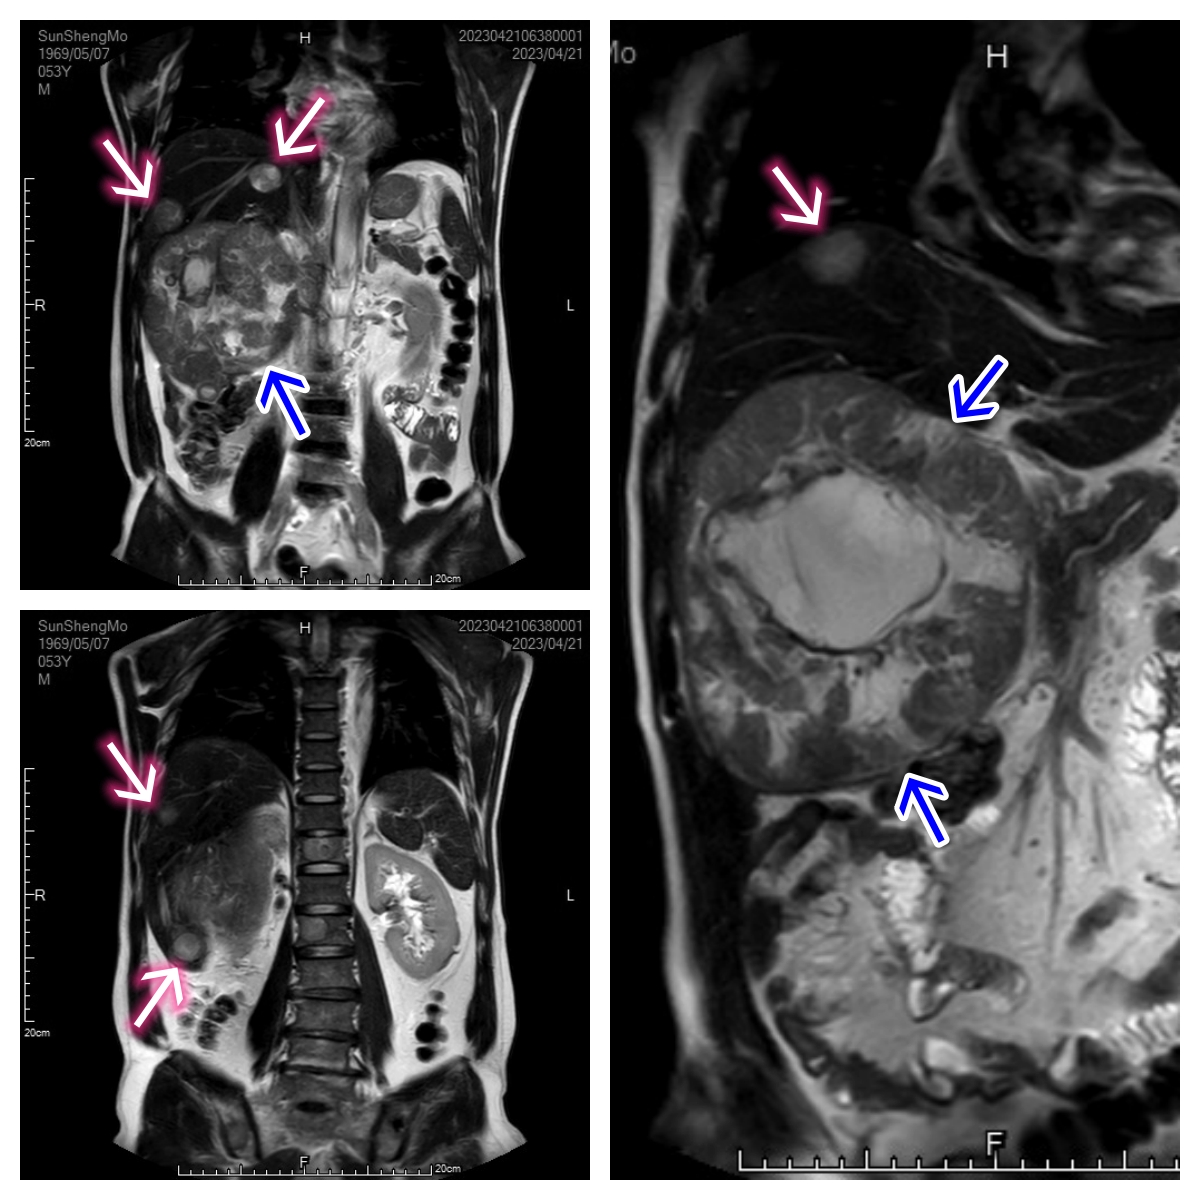

中年男性,右腹部胀痛3月余。MRI检查提示右肝巨块型肝癌并肝内多发子灶(4个),同时合并多发骨转移瘤。临床诊断分期:肝细胞癌(Ⅳ期)

MRI冠状位